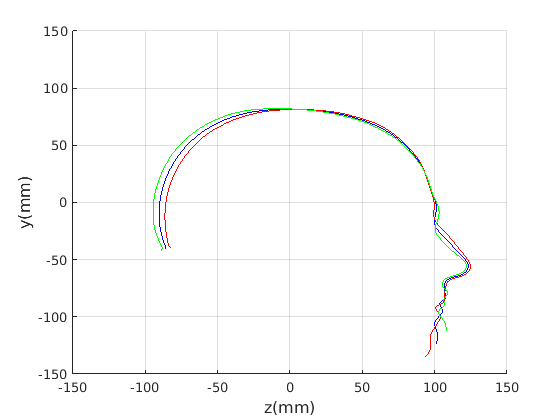

6.1 Modes of form and shape variation

We first demonstrate the dominant modes of shape variation over our training set. This is done for:

-

1.

The craniofacial profile : no scale normalisation (a form model).

-

2.

The craniofacial profile : with scale normalisation (a shape model).

-

3.

The cranial profile : no scale normalisation (a form model).

-

4.

The cranial profile : with scale normalisation (a shape model).

To emphasise the form/shape variation for each of these cases, the mean shape and shapes at mean for the four most significant modes of shape variation are plotted in Fig. 19 and Fig. 20. In this case, ECN normalisation is used.

For the craniofacial sagittal profile model, when not scale-normalised (Fig. 19, left column), the following four dominant shape modes are observed:

-

1.

Cranial height, calvarium convexity and facial angle constitute the main correlated shape variations captured im mode 1, with small cranial heights being correlated with a depression in the region of the bregma. There appears to be a waisting variation where the calvarium alternates between convex (high cranial height) and concave (low cranial height) configurations. Cranial height and ’waisting’ are also strongly correlated with the angle of the face relative to the line between the cranial ellipse centre and nasion.

-

2.

The overall size of the head varies : surprisingly this appears to be almost uncorrelated with craniofacial profile shape. This was only found in the ECN method of pose normalisation.

-

3.

The length of the face varies - there is variation in the ratio of face and cranium size.

-

4.

Variation in the chin size. A smaller chin appears to be correlated with a more prominent forehead.

The fact that the facial orientation appears to rotate initially led us to suspect a flawed pose normalisation procedure. However, the point about ECN normalisation is that it focuses on aligning the crania rather than faces, using its centre and the nasion, and the face has to follow that normalisation. Thus these results should be interpreted with a fixed cranial ellipse centre and fixed ellipse centre to nasion angle in mind.